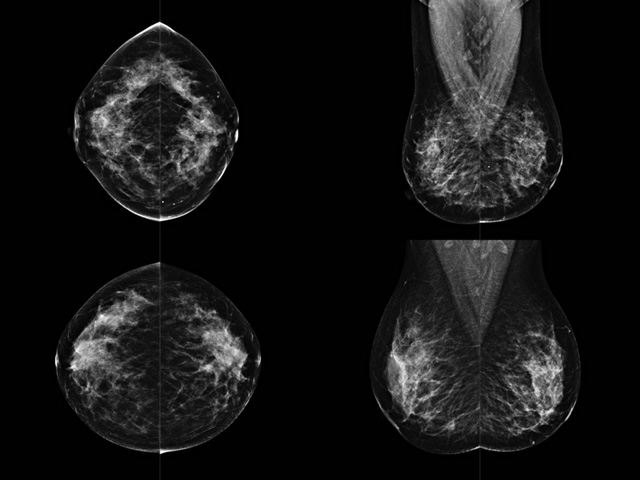

乳腺DR成像设备中非晶硅跟非晶硒两种平板探测器。更要提供优质的图像质量乳腺的组织结构与厚度各不相同,减少重拍率辐射剂量,,乳腺的主要构成组织均为软组织结构,组织之间密度十分相似,缺乏天然对比度。选择软X线摄影技术获得良好对比度的乳腺结构影像。增加各组织对X线的吸收差异。乳腺摄影测和分类,平板探测器的像素尺寸范围应在50到100μm之间。特别是微钙化灶可以小到100到200μm,平板探测器都必极小微钙化灶进行成像。

乳腺DR是利用X光来做检查,在一瞬间将被检测到的位置投影出来,因为是瞬间的辐射,所以只需要0.5秒的时间。因此对病人的辐射很低,大约是0.023mSv,比国家的标准要低得多。DR系统由 X线、发生装置、直接转换平板探测器、系统控制器、影像监视器、影像处理工作站等组成。能检查胸腔积液、肺结核、大叶性肺炎、肋骨骨折等。心室增大、主动脉扩张、主动脉瘤等心脏病。腹部病变,如肠梗阻、肠穿孔等,DR上可见液气平面、膈下游离气肿。DR表现不正常,要结合临床表现、体征、症状等综合分析,结合CT、彩超、血液分析等,才能作出正确的判断。